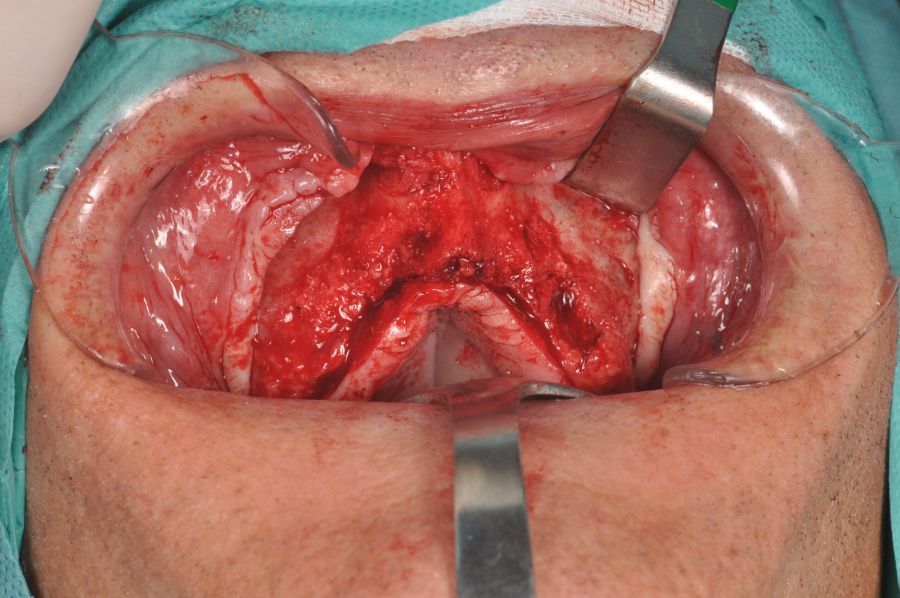

Under local anaesthesia, we disassembled the dentoalveolar hybrid prosthesis. It was only fixed by two implants that showed lower mobility. Periodontal curettage was performed in all areas adjacent to the lost implants and preprosthetic surgery to favour the closure of tissues with nonresorbable suture. A provisional complete prosthesis was placed during tissue healing time. Two months later, tissue healing was complete and no clinical signs of inflammation or pain were observed (Figure 2).